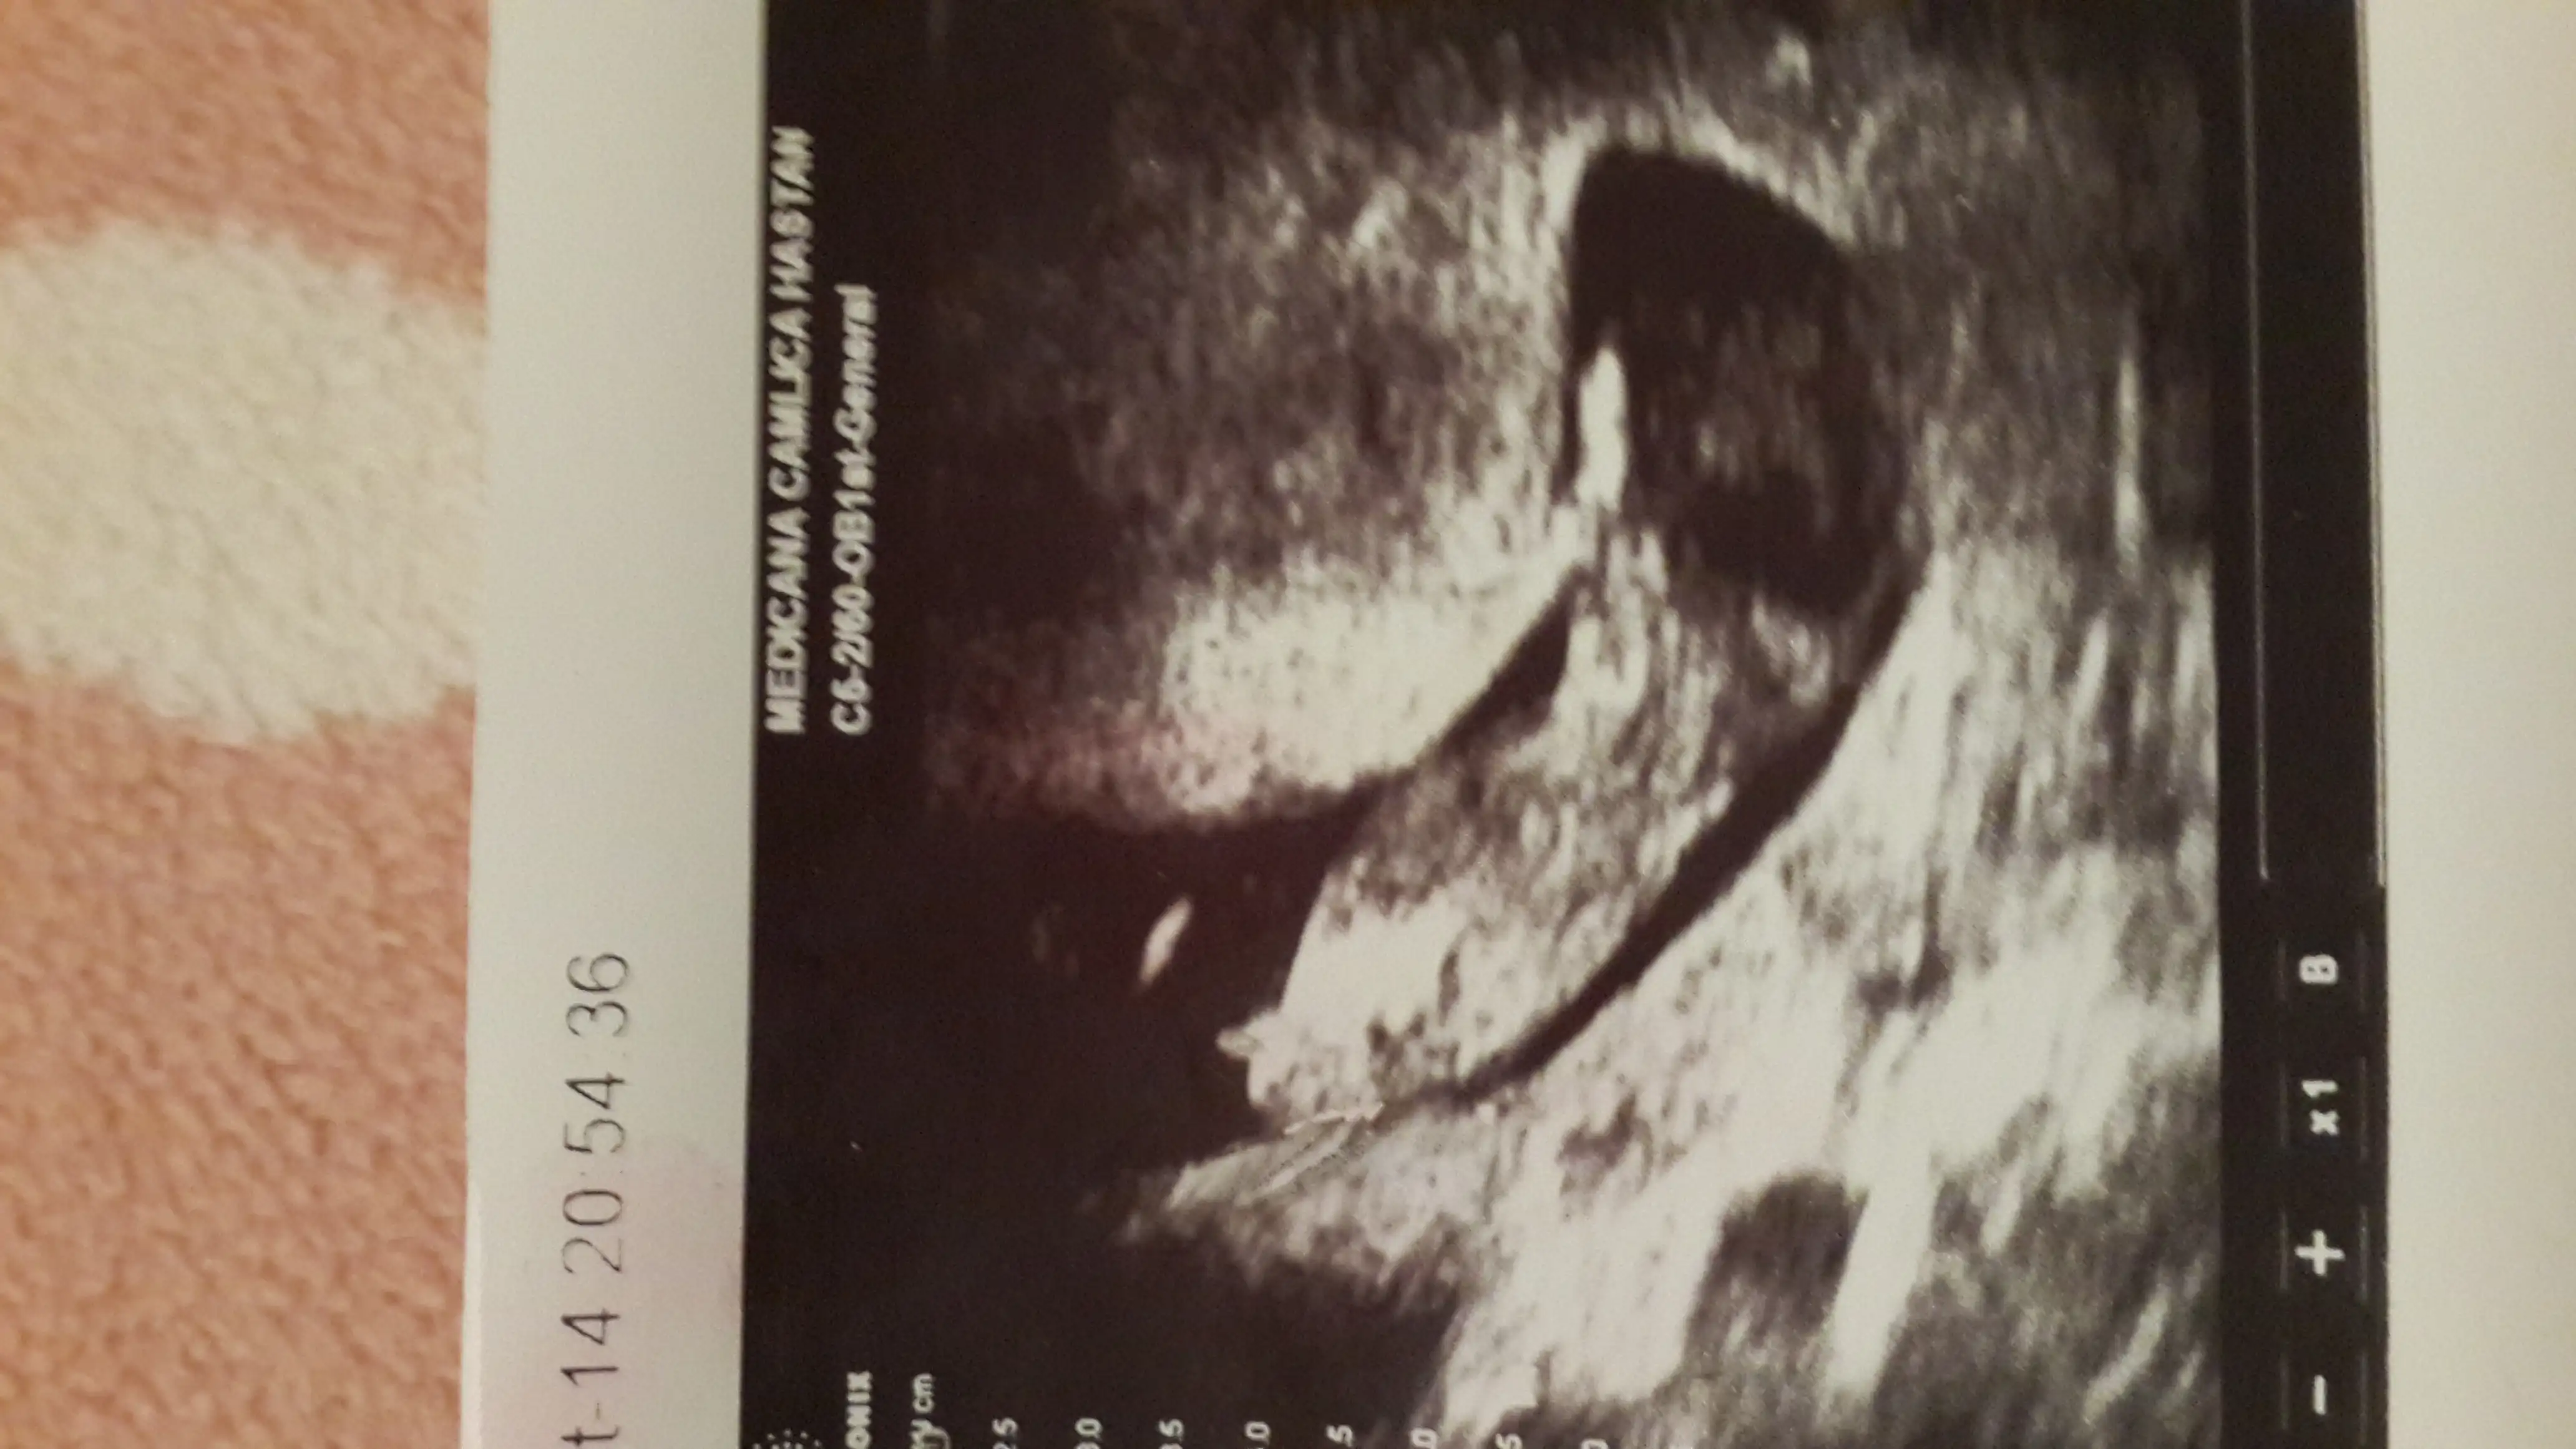

Kızlar neden kimse bana yorum yapmıyor nolur bide benim fotolara bakınboy ölçüm çizgisinin popo kısmından biraz yukarıda dik bir şey var gibi ama arkası dönük olduğu için kesin diyemiyorum.

Elimde bu pozisyonla ilgili baska bi foto yok malesef nub cikintisi popoya paralel mi geldi sizeSana

Kiz bu :)Elimde bu pozisyonla ilgili baska bi foto yok malesef nub cikintisi popoya paralel mi geldi sizeEki Görüntüle 1289060